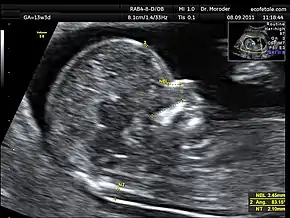

Nuchal fold thickness

Correct modified axial plane for the measurement of the nuchal fold in the second trimester[17].

Nuchal translucency testing is distinctly different from and should not be confused with nuchal thickness testing. At the end of the first trimester (14 weeks), the nuchal translucency can no longer be seen and instead the nuchal fold thickness is measured between 16 and 24 weeks gestation. The fold is more focal and at the level of the posterior fossa. This measurement has a higher threshold of normal, although the implications of increased thickness are similar to those of translucency. The nuchal fold thickness is considered normal if under 5mm between 16 and 18 weeks gestation and under 6mm between 18 and 24 weeks gestation. An increased thickness corresponds to increased risk for aneuploidy and other fetal abnormalities.